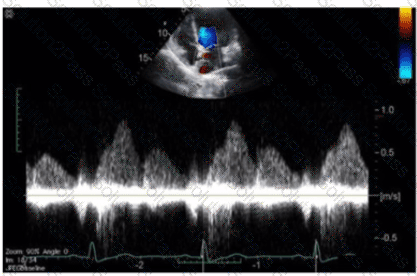

Which finding is best demonstrated in this video?